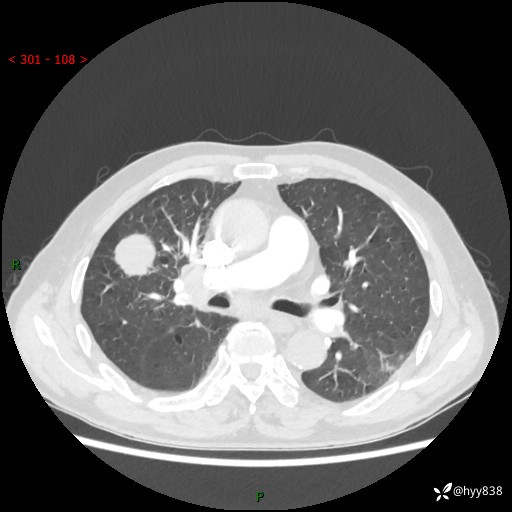

69岁/男,间断咳嗽伴气促、下肢水肿。临床拟诊肺栓,偶发肺均质强化结节--结果公布

【患者信息】:69岁/男

【主诉】:间断咳嗽伴气促、下肢水肿2周

【现病史及既往史】:患者2周来无明显诱因出现咳嗽,咳少量白痰,不易咳出,伴有气促,呈间断发作,症状与活动费力相关,以夜间为甚,不能平躺入睡,偶有憋醒,无胸闷胸痛、无发热、无头晕、头痛等不适,伴有双下肢中度水肿,就诊于当地县人民医院门诊,完善相关检查提示:左下肢深静脉血栓形成,未予以特殊处理,今患者为求进一步诊治来我院就诊,拟“心衰”收入我科。 起病以来,患者精神、饮食、睡眠可,大小便如常,体力明显下降,体重未见明显减轻。

【检查】:胸部CT增强